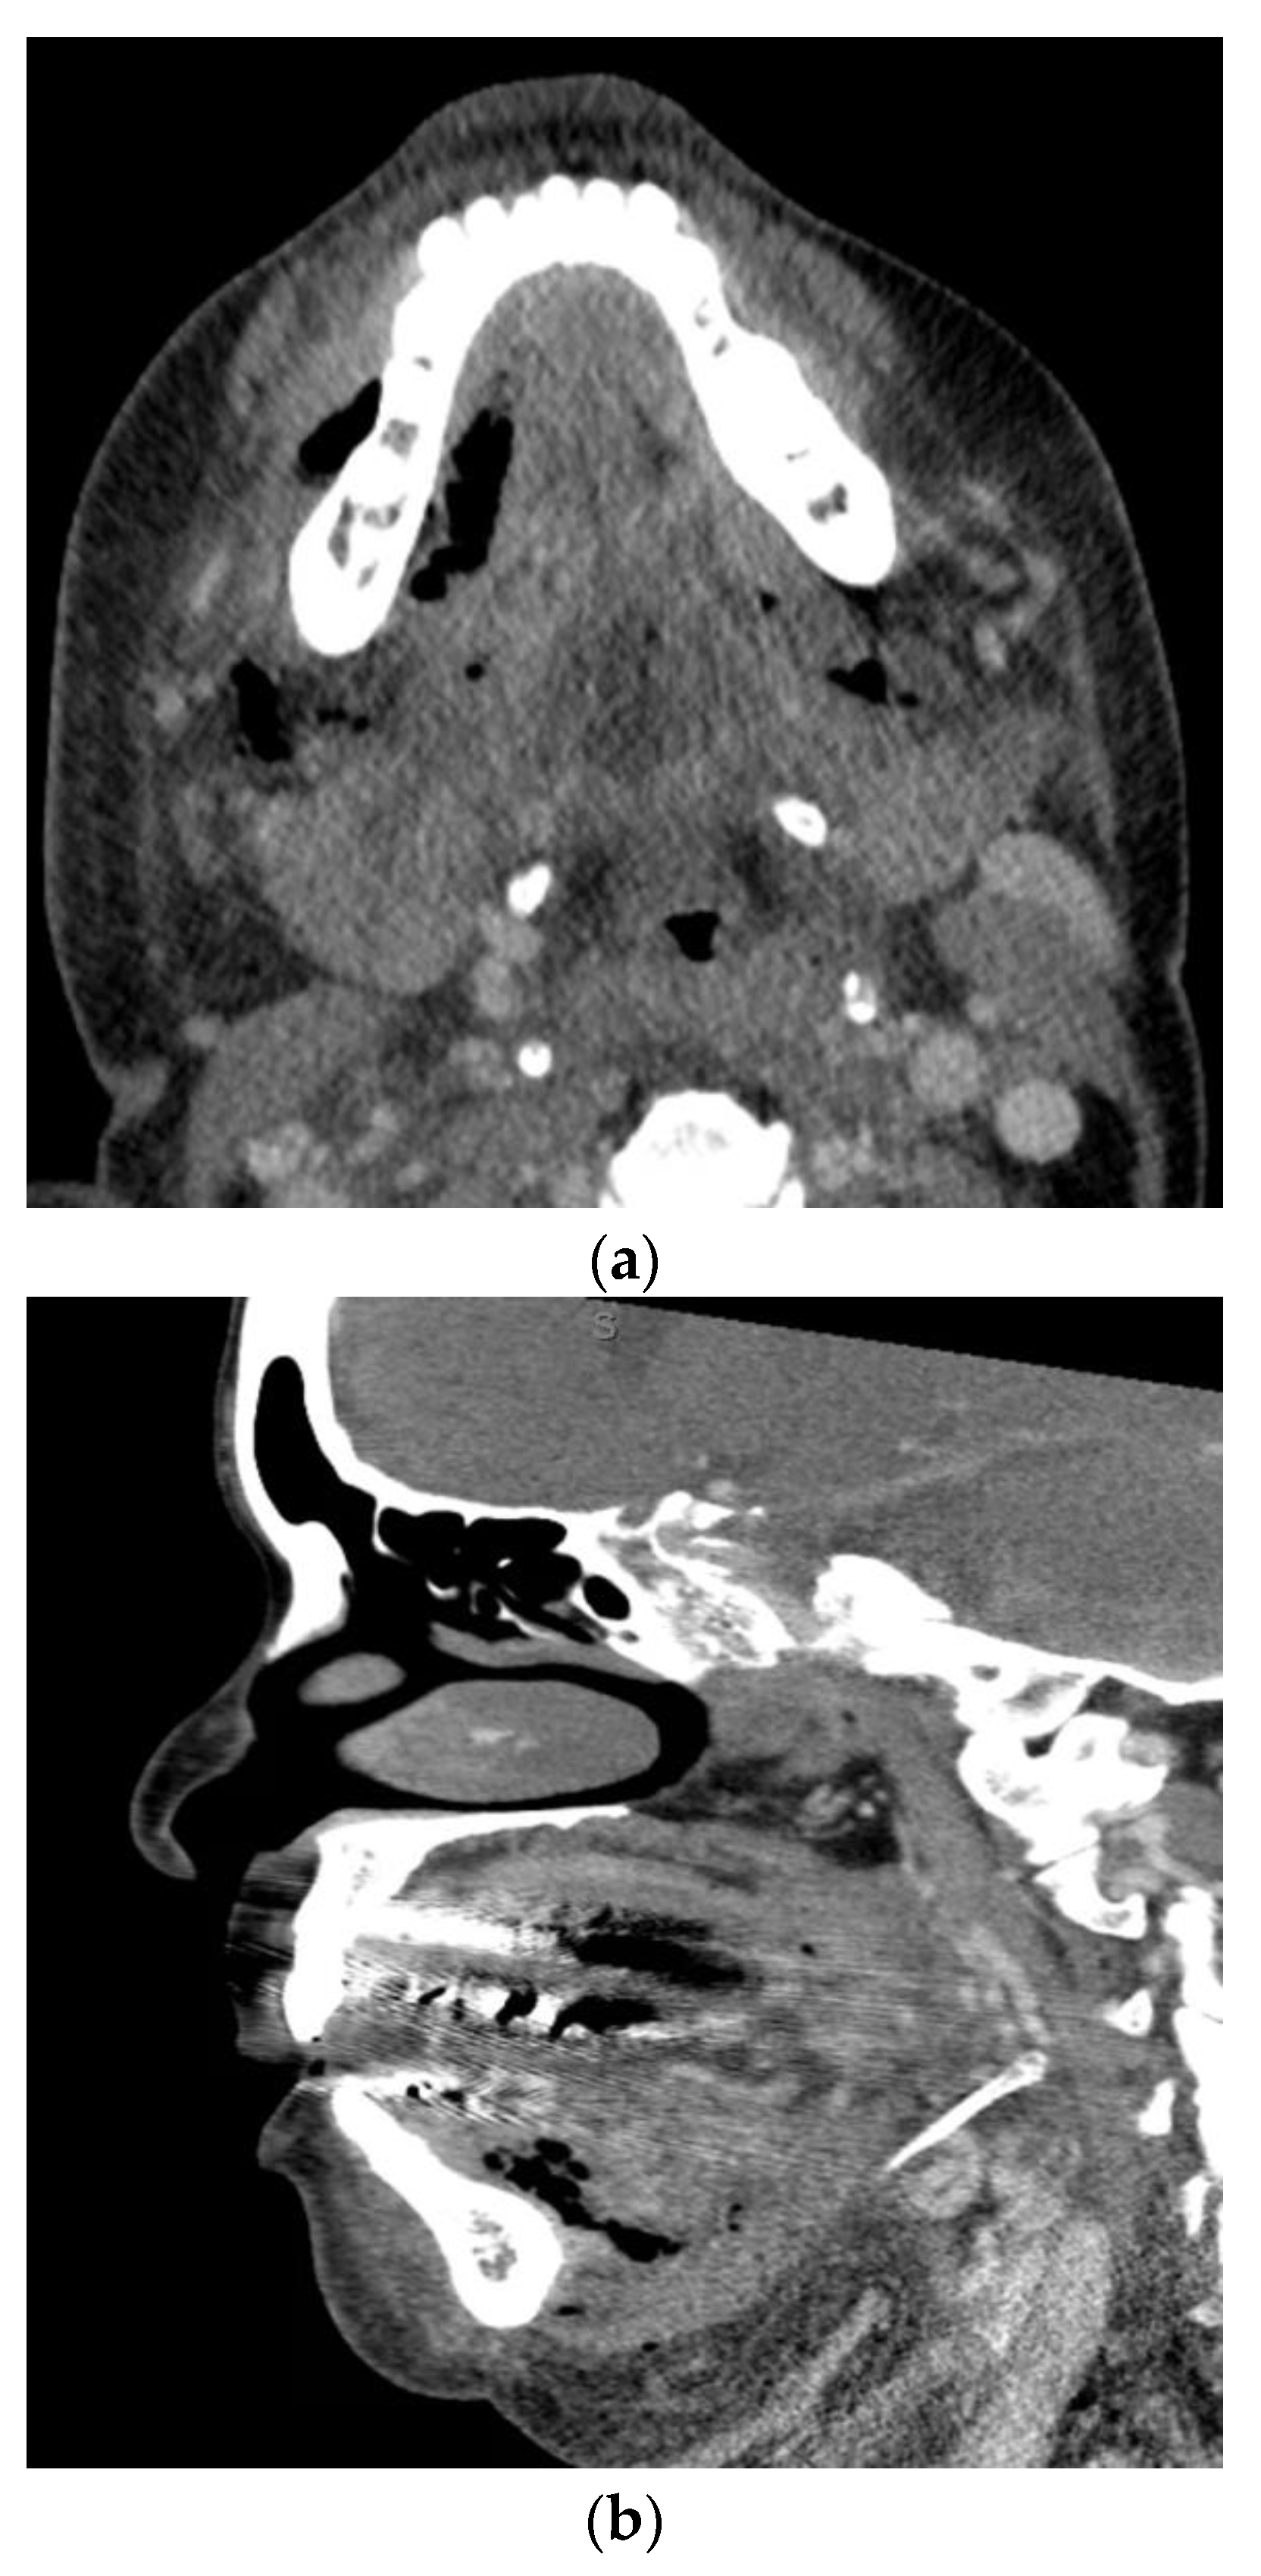

1.3. Descending Necrotizing Mediastinitis

1.4. Orbital Cellulitis, Abscess, and Septic Cavernous Sinus Thrombosis